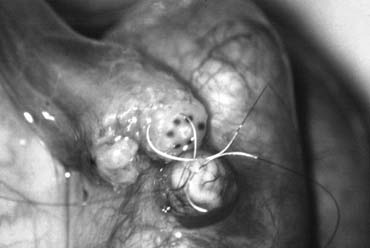

The specimen is then deposited directly into either Bouins, Zenkers, or collidine-buffered glutaraldehyde solution. Formalin fixation results in distortion of testicular histology and should not be used for testis biopsy. A touch-prep is made by blotting the cut surface of the testis several times with a glass slide (Fig. 4), and adding a drop of saline or lactated Ringer's and a cover slip. Examination under high power using a light microscope with or without phase contrast will reveal the presence of sperm with tails and allow assessment of motility (Fig. 5). If no sperm are found on the touch prep, a second specimen may be cut for a wet squash prep(Fig. 6). In this case, the specimen is placed on a slide, a drop of saline is added, and the specimen is crushed under a coverslip.28 If no sperm are found, the tunica is closed with two to three interrupted sutures of 6-0 nylon (Fig. 7) and another area undergoes biopsy through the same skin incision. As described later in this chapter, use of an operating microscope providing 10- to 25-times magnification may allow selective biopsy of larger seminiferous tubules more likely to contain sperm.15

Fig. 7. Closure of the tunica albuginia with interrupted 6-0 nylon.

If sperm are identified, the slide and additional tissue removed is sent for cryopreservation by the andrology laboratory. The location of the biopsy site and whether sperm were found at that site is noted in the operation report and the patients' chart. This facilitates identification of the sperm-bearing site for future IVF/ICSI with testicular extraction. The tunica albuginea is closed with two to three interrupted sutures of 6-0 nylon. Nonabsorbable sutures are used to aid in identifying the biopsy site at the time of future testicular sperm retrieval.